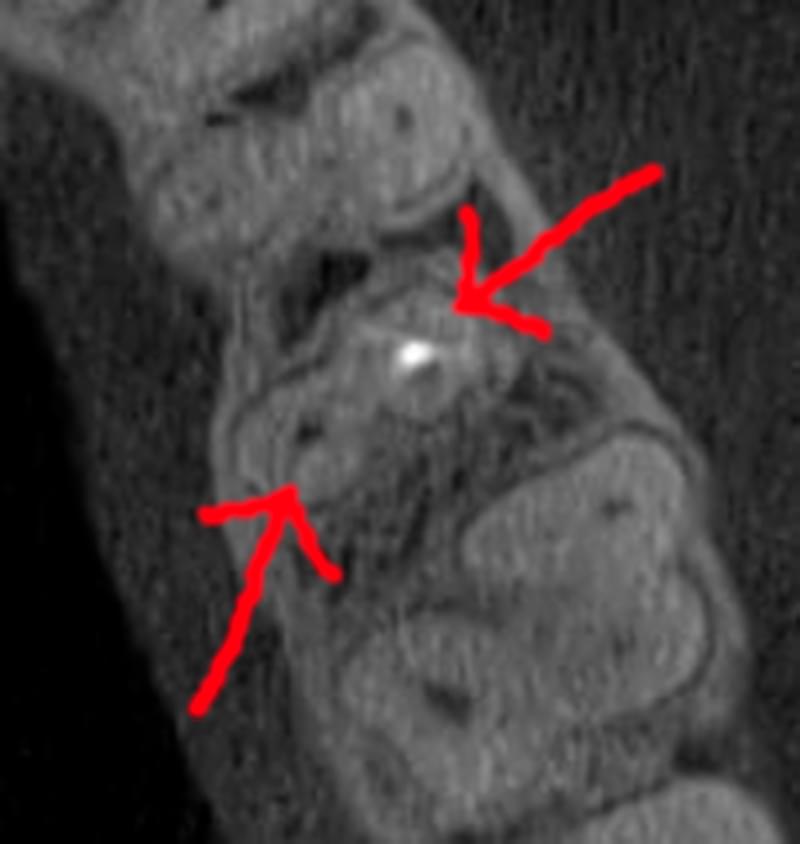

Коли коріння «ховає сюрпризи» - Корені зубів часто мають складну кривизну, гачкоподібні закручення або розгалуження, які на звичайному 2D-знімку накладаються один на одного, створюючи ілюзію прямого каналу. На плоскій картинці неможливо побачити реальний об'єм та напрямок вигину, що критично важливо при видаленні «зубів мудрості» або ендодонтичному лікуванні. КТ MyRay дає змогу лікарю заздалегідь побачити 3D-геометрію кожного кореня, оцінити його близькість до нижньощелепного нерва чи гайморової пазухи та підібрати правильну тактику роботи. Це мінімізує ризики поломки інструменту в каналі або травмування сусідніх структур, перетворюючи складну хірургію на прогнозовану процедуру.

Часто причиною зубного болю є гайморит, і навпаки — причиною запалення пазух є хворий зуб. На звичайному знімку пазуха виглядає як темна пляма. На КТ ми бачимо стан слизової, наявність кіст або сторонніх тіл (наприклад, залишків пломбувального матеріалу), що критично важливо для правильного діагнозу.